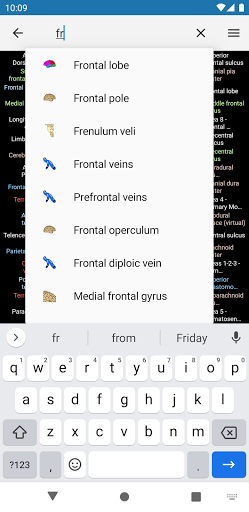

- Localice fácilmente las estructuras anatómicas gracias a la búsqueda de índice

*Encuentre sus partes anatómicas más fácilmente gracias a la nueva función de búsqueda, más intuitiva y poderosa.